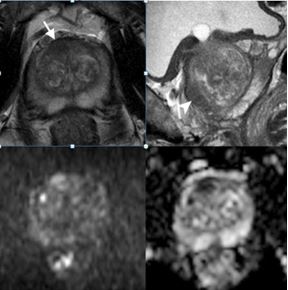

Evolution of prostate MRI

Using the available evidence and the evolution of PI-RADS, the authors reviewed the main technical strategies proposed as less-is-better solutions for clinical practice. The study also summarised research results on advanced techniques which represent an alternative different-is-better line of the still ongoing evolution of prostate MRI.

Article: Evolution of prostate MRI: from multiparametric standard to less-is-better and different-is better strategies